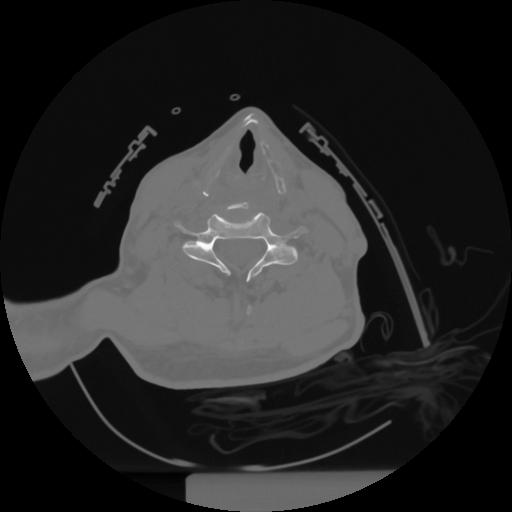

12 P.BLANDAS,,Vol,0.5,P.BLANDAS,,